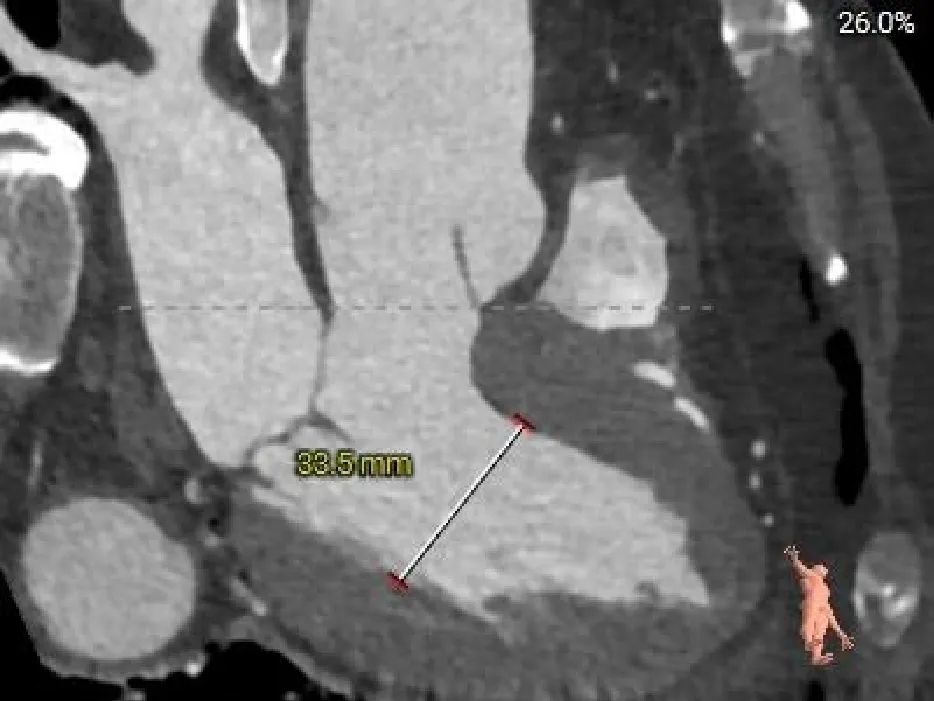

CASE Ⅲ

患者基本情况

基础信息:76岁,男性。

术前CT分析

主动脉根部测量

Annulus

25mm

LVOT

25.6mm

SOV

35.3*36.8*38.2mm

STJ

37mm

AAO

41.4mm

心脏角度

53°

纯反流三叶瓣,瓣环内径25mm

流出道直筒型

瓣叶无明显增厚、无钙化

升主动脉扩张

冠脉&左室评估

LCA & Leaflet

RCA & Leaflet

Left Ventricular

冠脉开口高度可,瓣叶稍长,结合瓦氏窦大小,预估冠脉风险相对较低

左室内径可,心室壁增厚